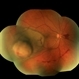

- Choroidal melanoma, brachytherapy, collar button

- 52 year old female at first visit July 2023 vs 7 months s/p brachytherapy. SRF in macula has resolved, trace fluid on posterior edge of collapsing collar button.